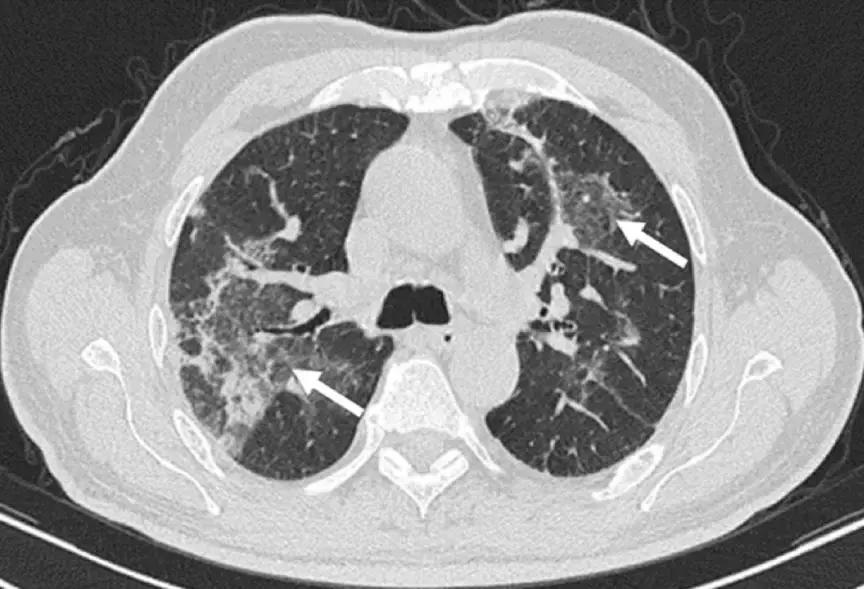

小叶间隔增厚:

小叶间隔增厚,伴中心型实变、GGO

反晕征:

结节或团块(需要和肿瘤鉴别):